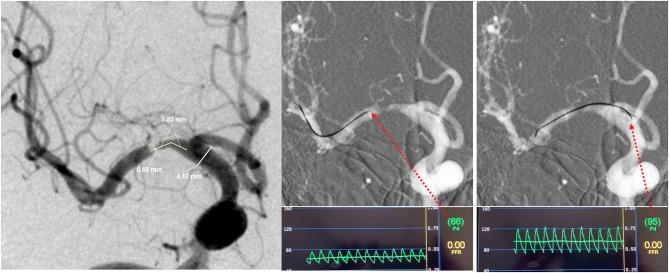

Intracranial cerebral atherosclerosis (ICAS) is a leading etiology of ischemic stroke. The diagnosis and assessment of intracranial stenosis are shifting from anatomic to hemodynamic for better risk stratification. However, the relationships between lesion geometry and translesional pressure gradient have not been clearly elucidated. Patients with symptomatic unifocal M1 middle cerebral artery (M1-MCA) stenosis were consecutively recruited. The translesional pressure gradient was measured with a pressure wire and was recorded as both mean distal/proximal pressure ratios (Pd/Pa) and translesional pressure difference (Pa-Pd). Lesion geometry measured on angiography was recorded as diameter stenosis, minimal lumen diameter, and lesion length. The correlations between pressure-derived and angiography-derived indices were then analyzed. Forty-three patients were analyzed. A negative correlation was found between Pd/Pa and diameter stenosis ( = -0.371; = 0.014) and between Pa - Pd and minimal lumen diameter ( = -0.507; = 0.001). A positive correlation was found between Pd/Pa and minimal lumen diameter ( = 0.411; = 0.006) and between Pa - Pd and diameter stenosis ( = 0.466; = 0.002). In a highly selected ICAS subgroup, geometric indices derived from angiography correlate significantly with translesional pressure gradient indices. However, the correlation strength is weak-to-moderate, which implies that anatomic assessment could only partly reflect hemodynamic status. Translesional pressure gradient measured by pressure wire may serve as a more predictive marker of ICAS severity. More factors need to be identified in further studies.

颅内脑动脉粥样硬化(ICAS)是缺血性卒中的主要病因。颅内狭窄的诊断和评估正从解剖学评估转向血流动力学评估,以实现更好的风险分层。然而,病变几何形状与跨病变压力梯度之间的关系尚未明确阐明。连续招募有症状的单灶性大脑中动脉M1段(M1-MCA)狭窄患者。使用压力导丝测量跨病变压力梯度,并记录为平均远端/近端压力比(Pd/Pa)和跨病变压力差(Pa-Pd)。血管造影测量的病变几何形状记录为直径狭窄、最小管腔直径和病变长度。然后分析压力衍生指标与血管造影衍生指标之间的相关性。对43例患者进行了分析。发现Pd/Pa与直径狭窄之间呈负相关(r = -0.371;P = 0.014),Pa - Pd与最小管腔直径之间呈负相关(r = -0.507;P = 0.001)。发现Pd/Pa与最小管腔直径之间呈正相关(r = 0.411;P = 0.006),Pa - Pd与直径狭窄之间呈正相关(r = 0.466;P = 0.002)。在一个经过高度筛选的ICAS亚组中,血管造影得出的几何指标与跨病变压力梯度指标显著相关。然而,相关强度为弱至中度,这意味着解剖学评估只能部分反映血流动力学状态。通过压力导丝测量的跨病变压力梯度可能是ICAS严重程度更具预测性的标志物。在进一步研究中需要确定更多因素。